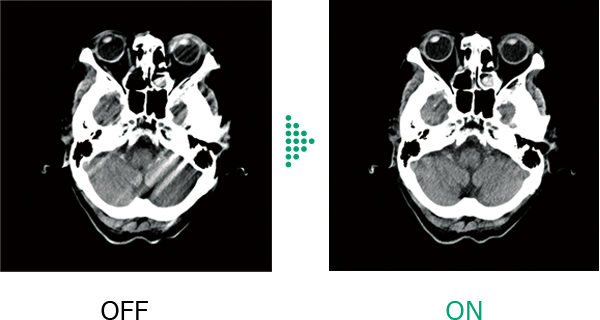

In head scanning, Body motion Correction corrects artifacts caused by patient movement.